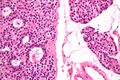

صورة مجهرية لغدوم الجار درقية (يسار) وغدة جارات درقية طبيعية (يمين). صبغة الهيماتوكسيلين واليوزين.